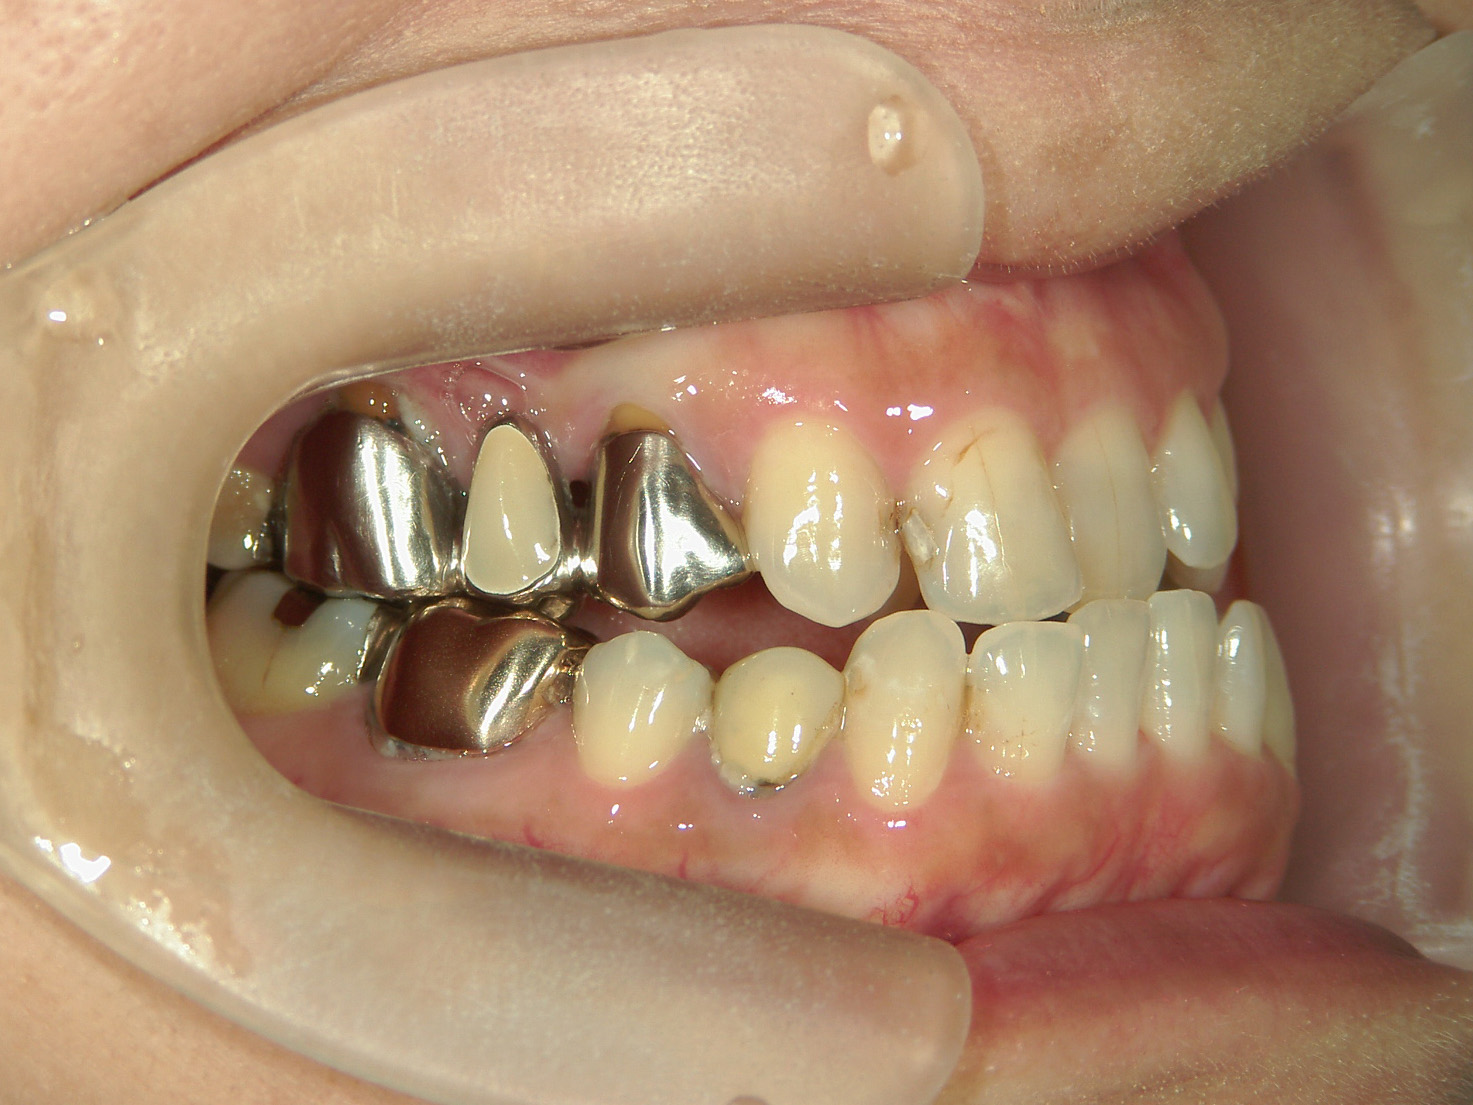

②右上前歯が内側に入っているため、歯列に入る隙間を作るためにワイヤー矯正を併用し、右上前歯を出しました。

③矯正装置を除去し、インビザライン矯正で歯列を整えました。